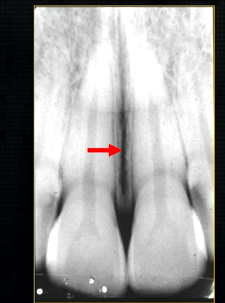

what does this anterior periapical graph show?

oval radiolucent area between the central incisors - is it Infront of the teeth (buccally?) or is it behind them? - you can’t tell radiographically

but its shape and position is compatible with the palatally positioned with the nasopalatine formaina

more posteriorly - radiopacities indicate the nasal septum and floor of the nose

dense, thin , white line in the middle of the image is the nasal septum

less dense opacity is caused by the

inferior nasal concha